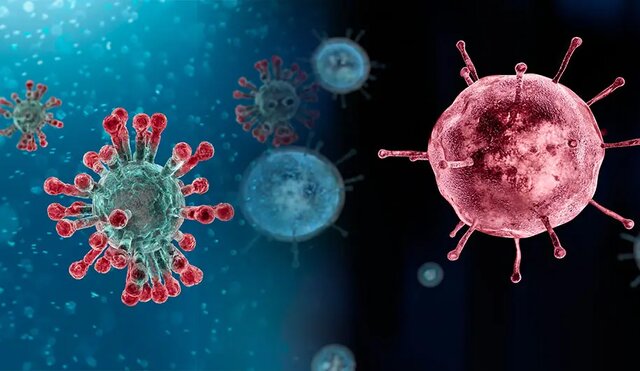

آلرژی فصلی شامل علائمی است که افراد در زمان های خاصی از سال تجربه می کنند. مخصوصا وقتی که درختان، علف ها و علف های هرز ذرات ریز گرده ی خود را در هوا آزاد میکنند تا گیاهان دیگر را بارور کنند. فصل زیبای بهار فصل جوانه زدن و گرده افشانی گیاهان و همین طور فصل تشدید حساسیت میلیون ها انسان است. اگر شما نیز یکی از همین افراد هستید، احتمالا آبریزش بینی، عطسه و سایر علائم آلرژی فصلی باعث رنج شما شده باشد که تب یونجه یا رینیت آلرژیک نیز نامیده می شود. به صورت کلی حساسیت بهار و تابستان در میان رایج ترین بیماری های بهار و بیماری های تابستان هستند.

علائم آلرژی فصلی تابستان، بهار و بقیه فصل ها بسیار آزاردهنده است و می تواند زندگی شما را مختل کند. خارش چشم، خارش بدن و همینطور آبریزش بینی از جمله علائمی هستند که در هنگام نزدیک بودن به عوامل حساسیت زا شروع و تشدید خواهند شد. از دیگر علائم که به واسطه ی آن ها می فهمیم آلرژی فصلی داریم می توان موارد زیر را نام برد.

درمان این نوع آلرژی فصلی امکان پذیر است و می توانید با رعایت نکاتی ساده از آن رهایی پیدا کنید، پس نیازی نیست نگران باشید، فقط کافیست نکات زیر را با دقت مطالعه و رعایت کنید تا رفته رفته از شدت علائم حساسیت های فصلی بکاهید. لازم به ذکر است که اگر علائم شما شدید باشد در کنار رعایت نکات زیر حتما با پزشک نیز مشورت کنید و بدون تجویز پزشک هیچ دارویی را مصرف نکنید حتی اگر آن دارو بدون نسخه نیز در دسترس باشد. سامانه ی دکتر مایکو با امکان برقراری ارتباط حضوری و آنلاین با پزشکان بیمارستان ها و کلینیک ها در رفع این مشکلات و علائم شما را یاری می کند.